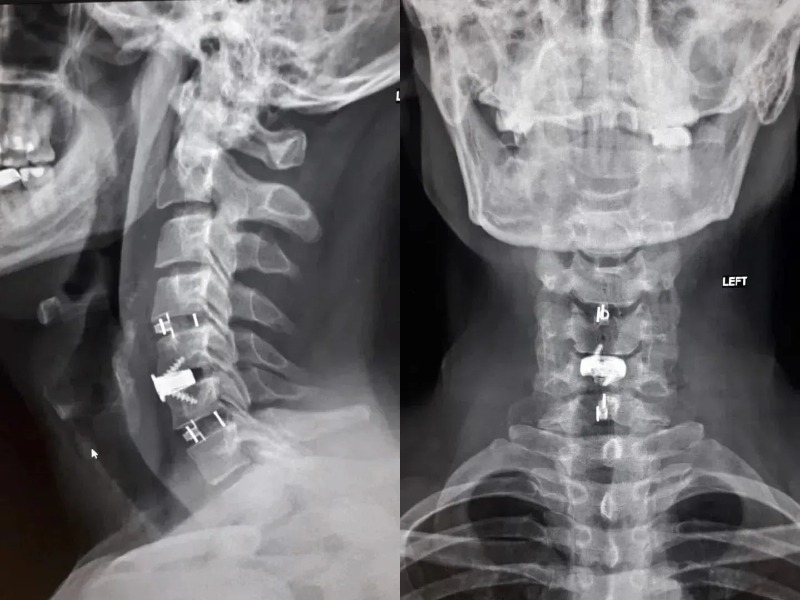

В стационаре БСМП №1 мужчине диагностировали «диско-остеофитный стеноз позвоночного канала на уровне C3-C4, C4-C5, C5-C6, C6-C7». У него на уровне ряда шейных позвонков произошло сужение, а находящиеся в нём структуры сдавливались.

«Уникальность операции заключалась в комбинированной технике. Медики во главе с заведующим нейрохирургическим отделением Павлом Юровым устранила сжатие и стабилизировала позвоночник, одновременно с этим укрепив его разными титановыми конструкциями», – отметили в Минздраве.